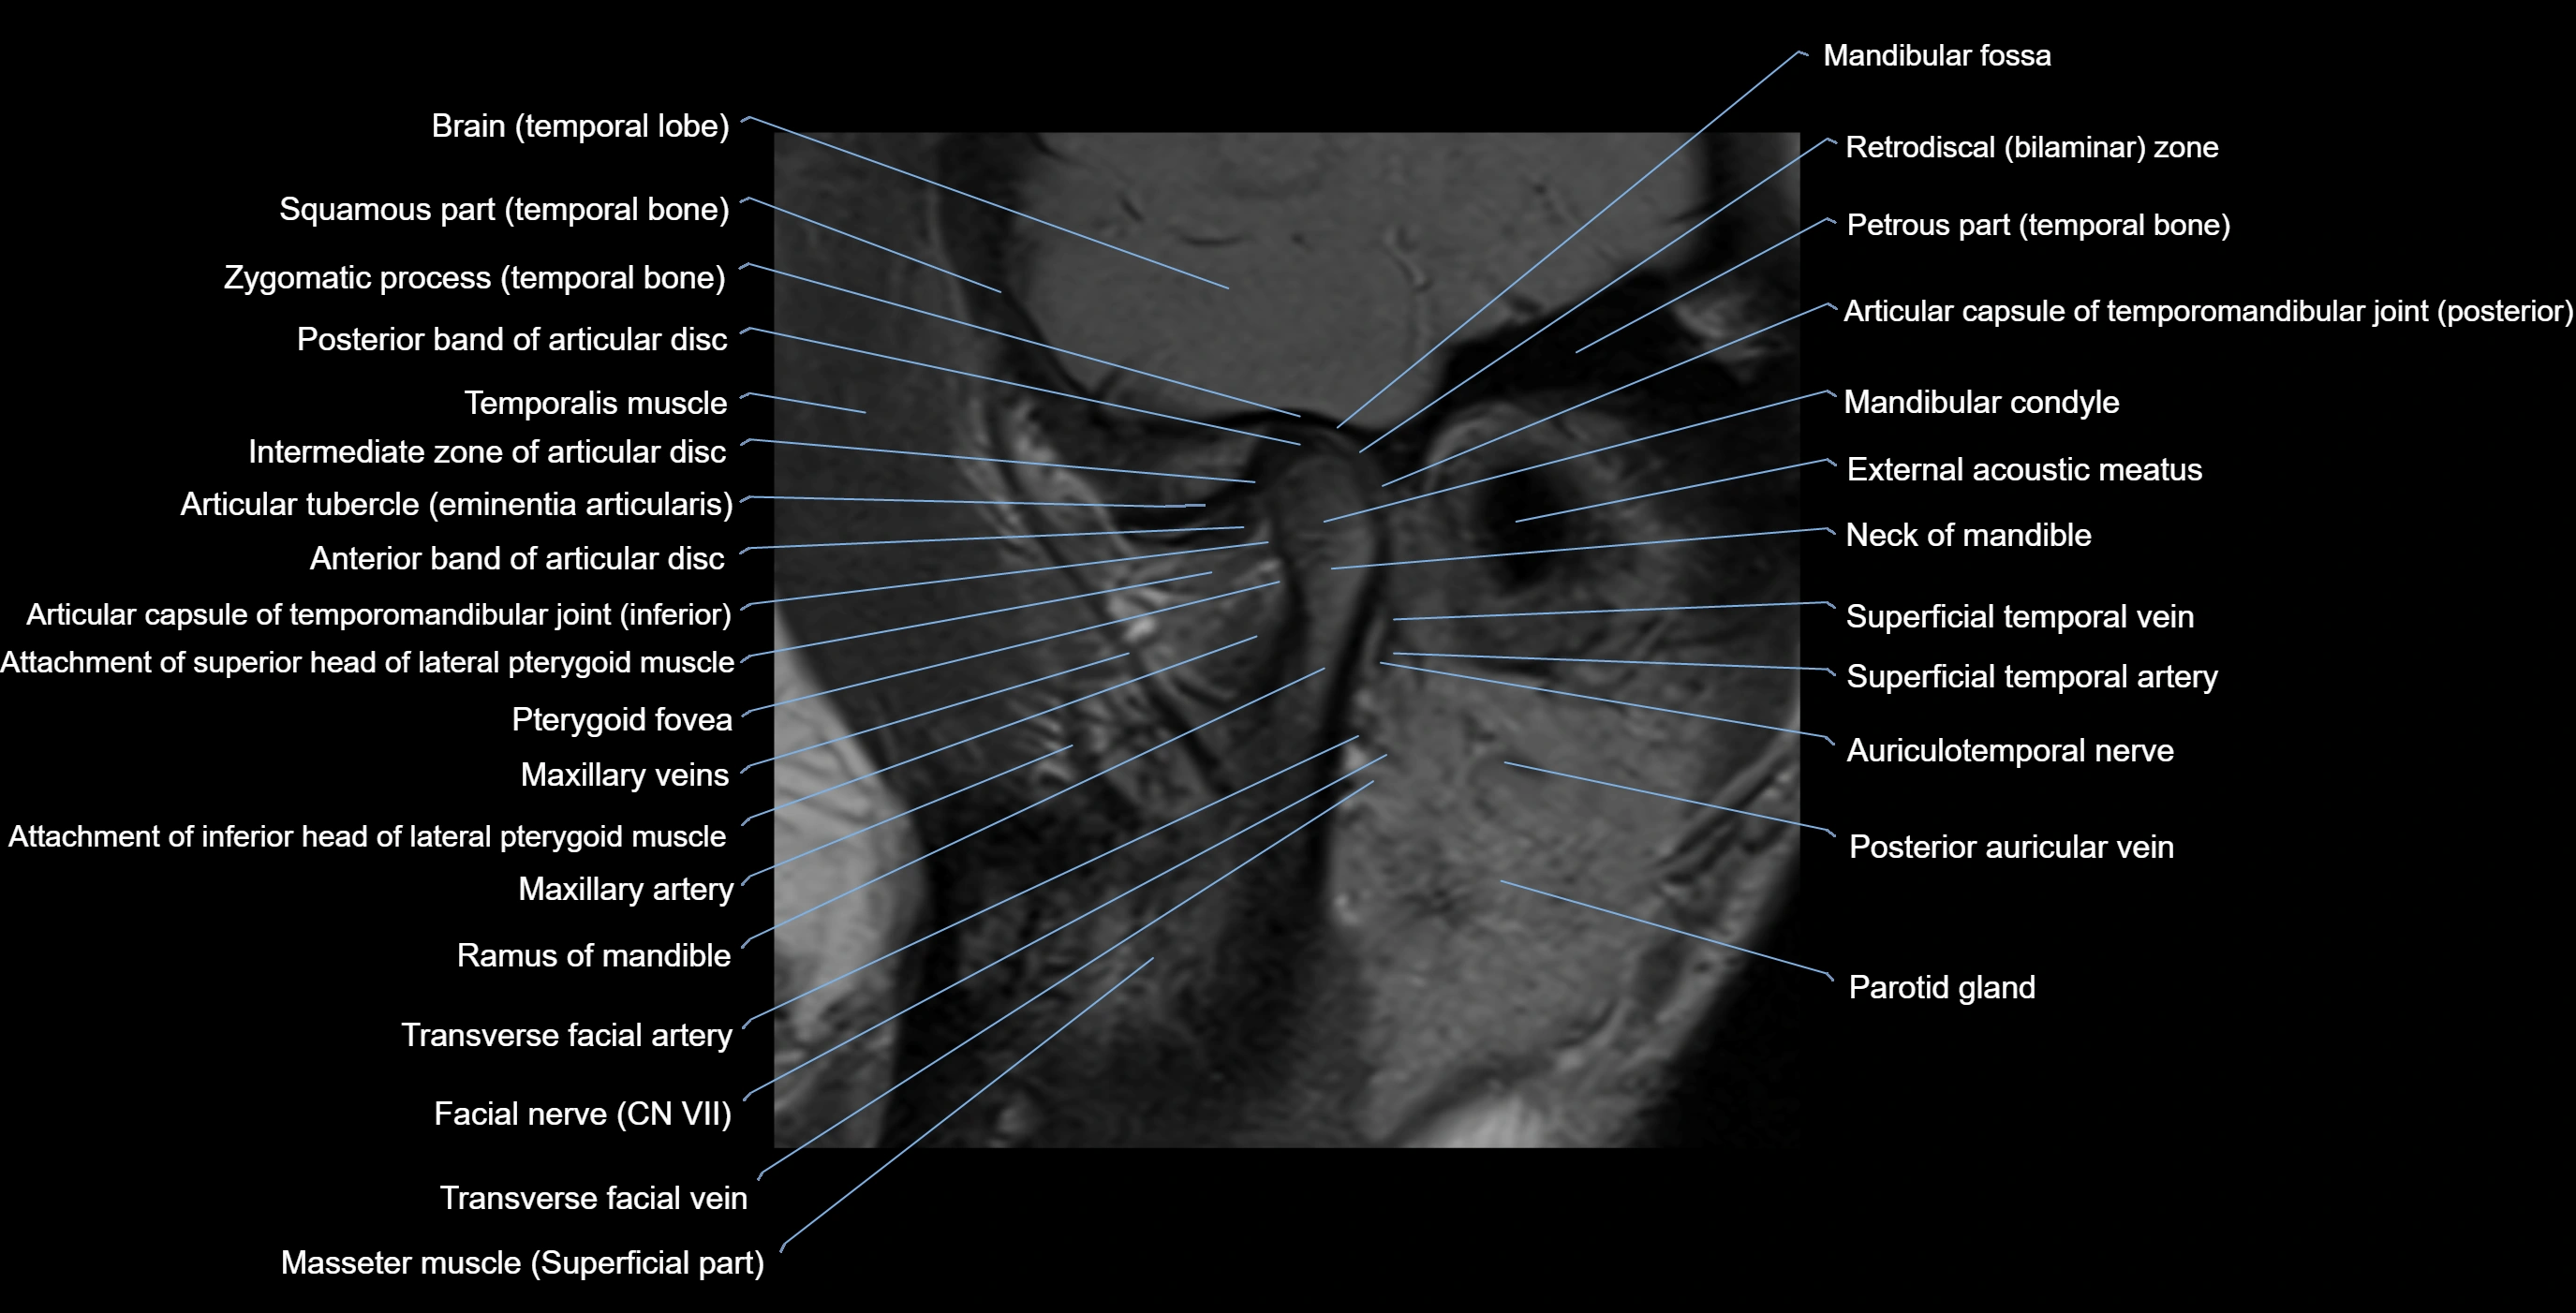

MRI appearance

T1-weighted images:

• Cortical bone: Low signal intensity

• Cancellous marrow: Intermediate to high signal depending on fatty content

• Teeth: Signal void structures

• Adjacent soft tissues: Normal gingiva and oral mucosa signal

T2-weighted images:

• Cortical bone and teeth: Low signal

• Marrow: Intermediate signal